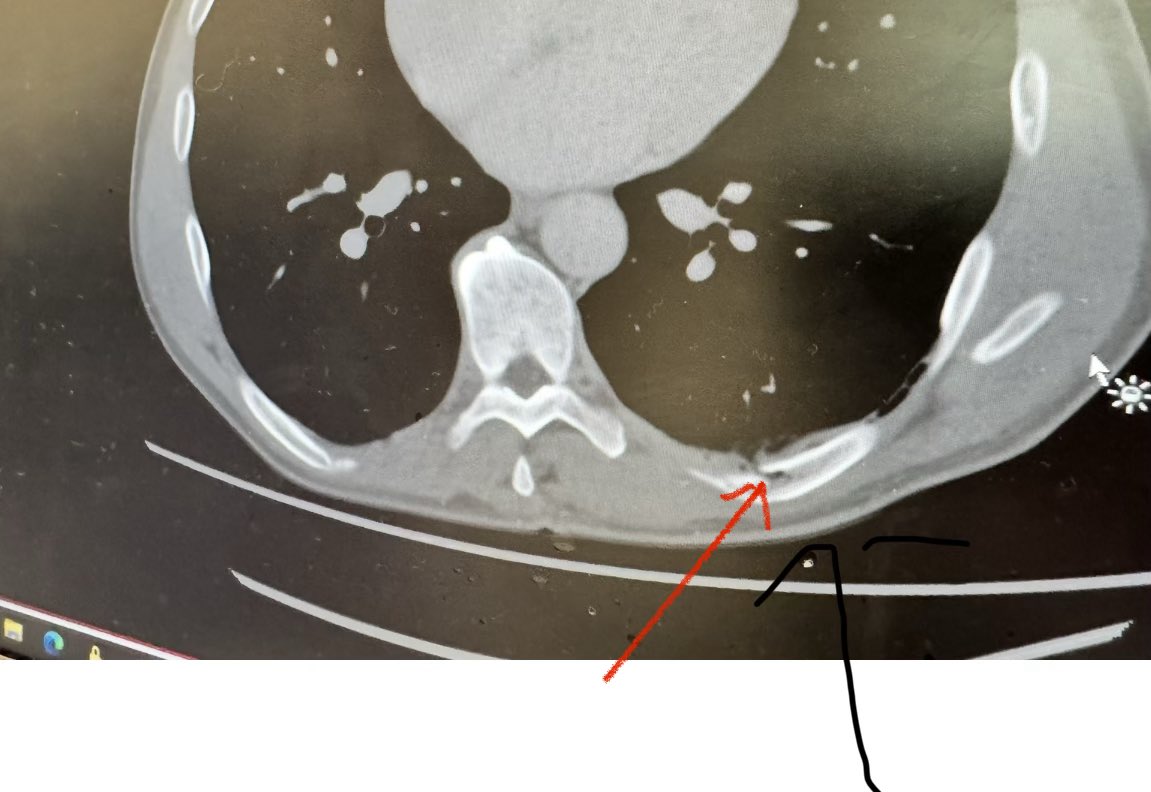

I am really excited about the Tour de Cure’s cycling event coming up in six weeks time in Tasmania. I’ve been training hard but unfortunately I threw a “spanner in the works” when I slipped while I was on a jog. I fractured a couple of ribs and developed a pneumothorax (air leaking out of my lungs into some adjacent tissue) which is holding things back. But despite this, I remain as determined as ever. I can’t wait to get back to training hard again soon!